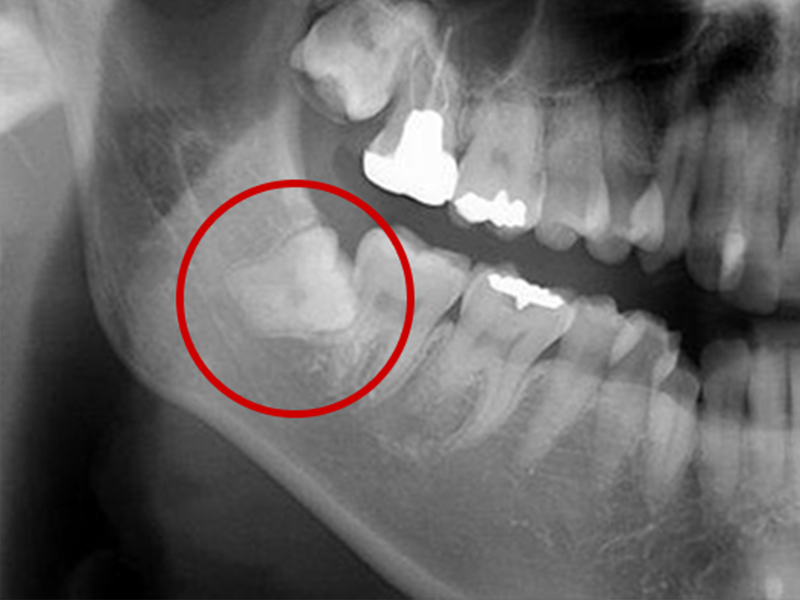

親知らずとは大臼歯(大人の奥歯)の中で一番後ろに位置する第3大臼歯です。

智歯とも呼ばれ20歳前後で生えてくることが多く、一般的には上顎の左右2本と下顎の左右2本計4本ありますが、もともと親知らずのない人や4本そろっていない人など、個人差があります。

親知らずによる痛みの原因

親知らずは横や斜めに生えてきたり、歯ぐきがかぶっていることがあります。そのため親知らずの周囲には細菌が残りやすく、トラブルを起こし、痛みの原因になります。

親知らずが周囲に以下のような悪影響をもたらしている場合は、早めの抜歯をおすすめします。